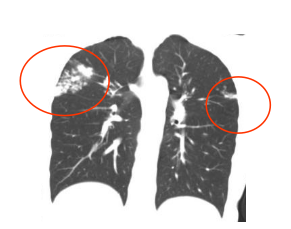

2026年2月,小东肺部CT显示:异常